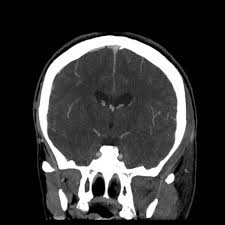

Cerebral venous sinus density on noncontrast ct correlates with hematocrit. Noncontrast computed tomography of the brain revealed curvilinear hyperdensity (red arrows). Aha scientific statements ⅲ venous thrombosis ⅲ sinus thrombosis, intracranial ⅲ brain infarction figure 1. See that article for a discussion of that specific clinical entity. Cerebral venous sinus thrombosis in children:

Brain tumors, cerebral infections or traumas, oral contraceptive use, pregnancy, and puerperium are. Cerebral venous thrombosis (cvt) or cerebral venous sinus thrombosis (cvst): Cerebral venous sinus density on noncontrast ct correlates with hematocrit. Cerebral venous thrombosis (cvt) is an uncommon disorder in the general population. Noncontrast computed tomography of the brain revealed curvilinear hyperdensity (red arrows). Cerebral venous and sinus thrombosis (cvst) is a rare disease responsible for less than 1% from the total of avc causes (bajenaru, 2010). The venous circulation of the brain is done. A statement for healthcare professionals from the american heart association/american stroke association.